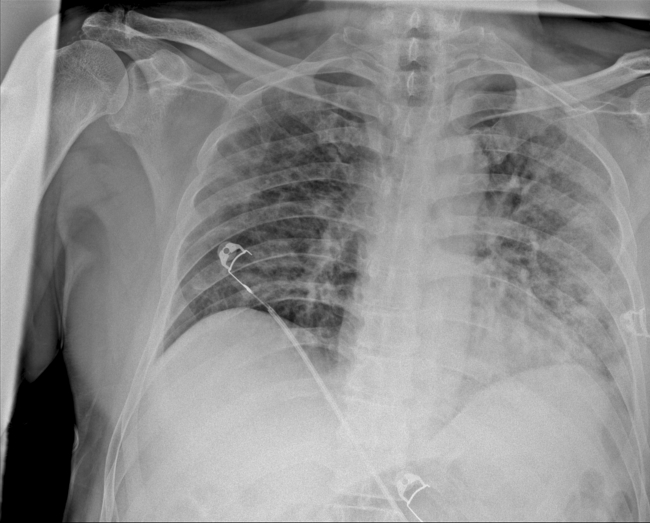

Prof. Dr. Karalezli, koronavirüs tedavisi gören hastalara ait akciğer görüntülerinden hastalığın yol açtığı tahribatı ve hastalar üzerindeki etkileri anlattı.

Tedavisine rağmen nefes darlığı şikayetleri devam eden bir hastaya uygulanan akciğer görüntülemesinde hastanın her iki akciğerinin büyük bir bölümünü enfeksiyon kapladığını tespit ettiklerini ifade eden Karalezli, "Bu hastalığın sonunun ne olduğunu bilmiyoruz. Akciğer tutulumları, bu şekilde olduğu zaman hastaları oksijen tedavisi ile gönderiyoruz. Çok yeni bir hastalık olduğu için bu seyir nasıl olacak? Geriye dönüş var mı? Takiplerle öğrenebileceğimiz bir durum." dedi.

Normal akciğer görüntüleri ile koronavirüs hastalarının akciğer görüntüleri arasında ciddi farklar bulunduğunu belirten Karalezli, şu bilgileri verdi:

"İnsanların aradaki farkları anlamaları için her iki akciğer görüntülerine de yer verdim. Görüntülerdeki beyazlıklar akciğerdeki tutulumu gösteren görüntüler ne yazık ki. Bu hastalar yoğun bakım hastaları. Filmler birbirine az çok benzeyen şekilde. Altta yatan hastalığı olanlarda ise daha kötü seyrediyor."

Kliniğe yeni başvuran bir hastanın, 5 Ağustos'ta çekilen tomografi görüntülerindeki tipik koronavirüs görüntülerinin olduğunu ifade eden Karalezli, hastanın bir hafta içerisindeki tomografi görüntüsünde ciddi değişiklik olduğunu ve enfeksiyonun çok arttığını söyledi.